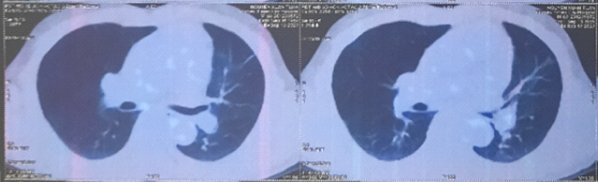

Hình 3: Nhu mô hạ phân thùy VII có vài khối, nốt kích thước lớn nhất 33x26mm giảm tỷ trọng trước tiêm, ngấm thuốc thì động mạch (vòng tròn đỏ), thải thuốc thì tĩnh mạch cửa (vòng tròn).

Cắt lớp vi tính ổ bụng có tiêm thuốc cản quang:

Hình 8: Hình ảnh khối tăng chuyển hóa FDG ở gan phải/gan xơ, phù hợp với tổn thương ác tính (có thể thứ phát từ u phổi hoặc ung thư biểu mô tế bào gan) (vòng tròn đỏ) (cMx).